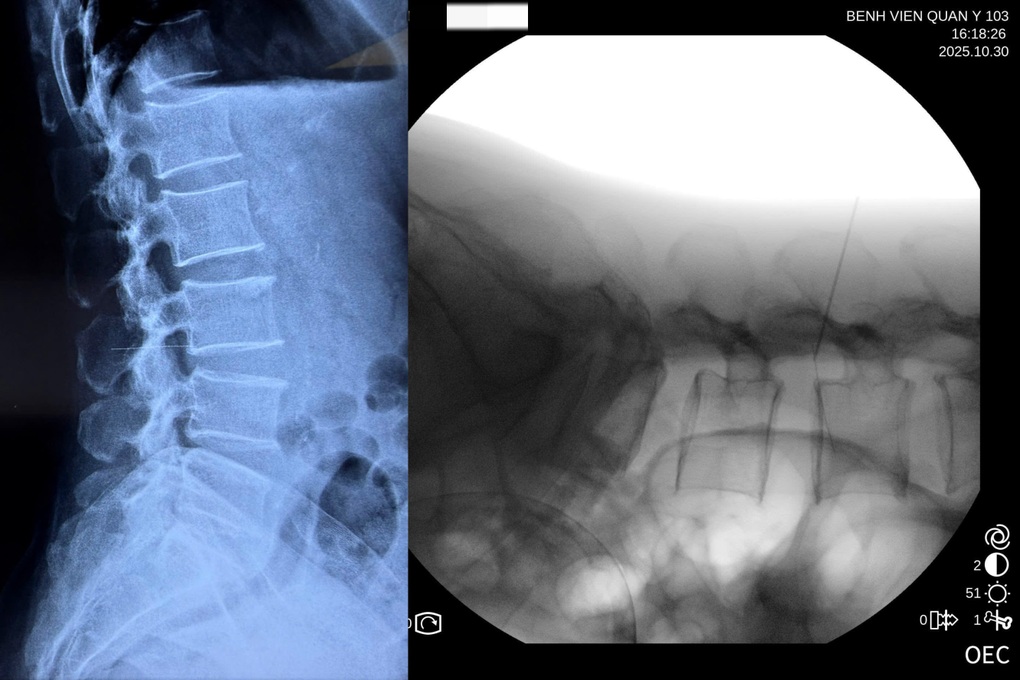

Qua thăm khám lâm sàng, các bác sĩ phát hiện nhiều nốt kim châm xung quanh vùng thắt lưng. Kết quả chụp X-quang phát hiện một dị vật kim khí cắm sâu theo chiều thân đốt sống.

Qua khai thác bệnh sử, bệnh nhân cho biết khi thấy đau ở vùng thắt lưng đã tự dùng kim châm cứu. Một đoạn kim châm dài 6cm đã bị gãy, đâm dọc vào đốt sống của bệnh nhân.

Ảnh chụp X-quang phát hiện đoạn kim gãy đâm dọc vào đốt sống của bệnh nhân (Ảnh: Bệnh viện cung cấp).